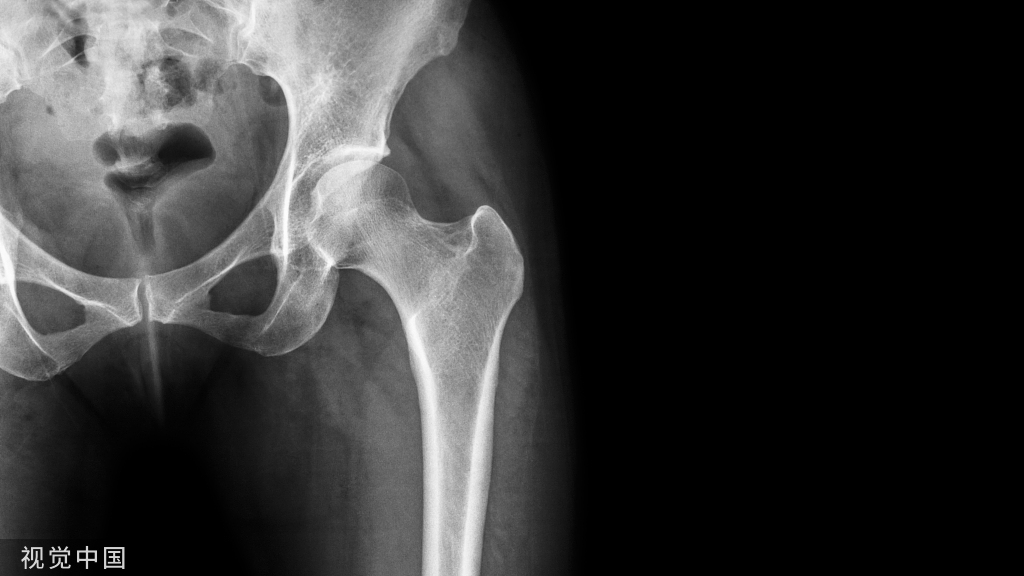

如果坎墩严重,需要先植入椎弓根螺钉,咬除部分后方椎板,进行后柱的撑开。

先植入能植入的椎弓根螺钉, 深度过椎弓根即可

先进行短阶段的撑开,撑开之后暴露关键的前移的椎体再植入椎弓根螺钉进行二次撑开

要点:进行初次撑开之后,取下一侧的棒,植入关键椎体的椎弓根螺钉再换另外一侧,同法。